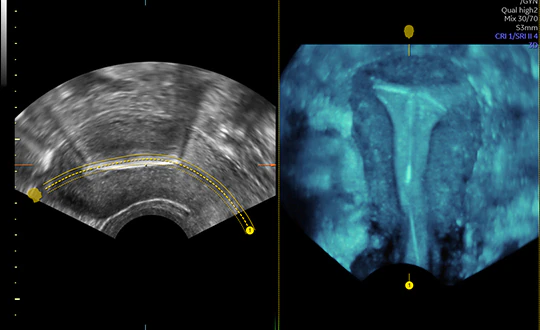

ECOGRAFIA GINECOLOGICA

Lo studio del Prof. Susini dispone di uno strumento diagnostico evoluto dotato di Intelligenza Artificiale che acquisisce immagini di altissima precisione e che permette di valutare tutti gli aspetti della salute della donna, da quelli per la prevenzione a quelli più complessi.

Il livello ottimale di imaging migliora l’affidabilità diagnostica e consente di fornire alla paziente referti ed esami efficienti, in quanto raccoglie immagini 2D, 3D e 4D con uno straordinario dettaglio clinico, fornendo una vista completa e precisa dell’anatomia, mette a fuoco anche la più minuscola struttura e permette di visualizzare le strutture vascolari dai piccoli vasi alle grandi arterie. Uno strumento così valido e all’avanguardia che ottiene in modo chiaro le immagini e le misurazioni, consente di avere la possibilità di rilevare e diagnosticare precocemente i problemi, permette lo studio NON INVASIVO di utero e ovaie per una valutazione assai precisa dei fibromi uterini dei polipi endometriali e delle malformazioni uterine ed intervenire tempestivamente con eventuali terapie, aumentando la soddisfazione e la tranquillità della paziente.